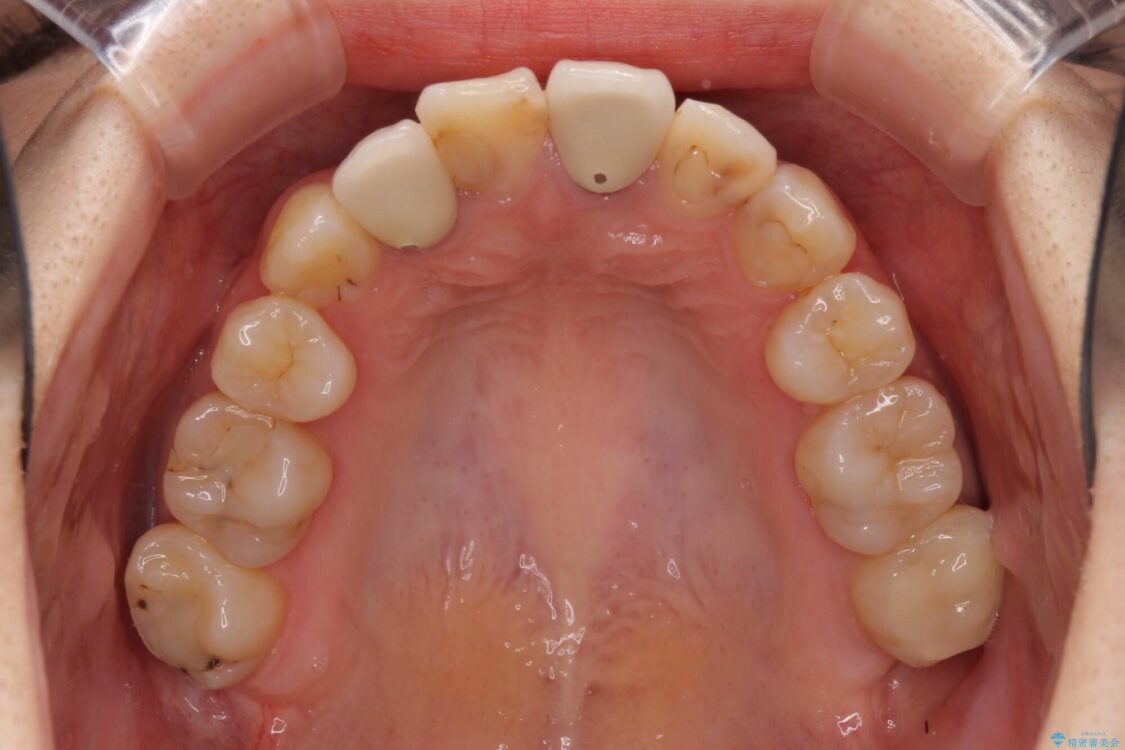

治療前

• 虫歯治療ついでに歯並びの後戻りを改善 インビザラインによる矯正治療 治療前画像